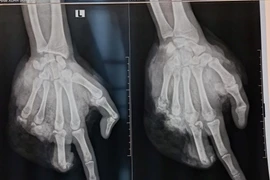

Dập nát 1 bàn tay do pháo tự chế phát nổ

Bé trai nhập viện cấp cứu với bàn tay bị xẻ đôi vì tự chế pháo nổ